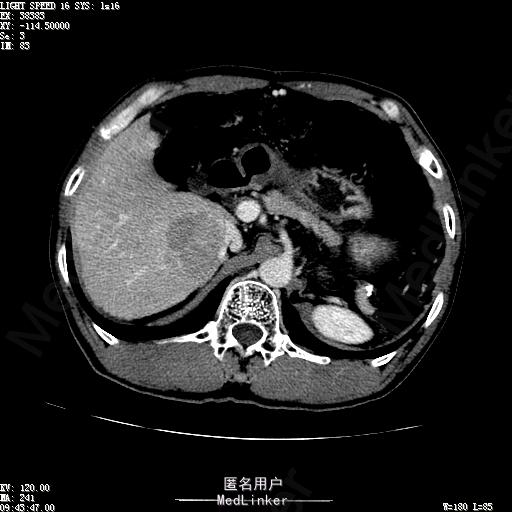

查体:体温36.4℃,脉搏76次/分,呼吸18次/分,血压110/70mmHg。神志清晰,发育正常,营养中等,体位自如,表情安静,慢性病容,检查合作。皮肤粘膜颜色正常,无瘀点、紫癜,有肝掌,无蜘蛛痣,无水肿,毛发的生长与分布正常。浅表淋巴结浅表淋巴结未触及肿大。无巩膜黄染,结膜正常。口唇红润,粘膜正常,舌正常,牙龈正常,扁桃体无肿大,无咽部充血。颈部外形对称,颈静脉正常,肝颈静脉回流征阴性,气管居中。甲状腺正常,无颈部血管杂音。胸部形态正常,呼吸运动平稳规律,无呼吸困难,肋间隙正常。触诊语颤正常,无胸膜摩擦感,肺下界位于右锁骨中线第六肋间。呼吸音正常,未闻及干湿啰音,无胸膜摩擦音。无心前区隆起,心尖搏动正常,心率:76次/分,心律齐,心音正常,无杂音,无心包摩擦音。无大动脉及周围血管征,无奇脉及交替脉,无水冲脉,无枪击音,腹型对称,无腹壁静脉曲张,未见胃肠型及蠕动波,无瘢痕,脐部正常。无压痛,无反跳痛,无腹肌紧张,无腹部包块。肝未触及,Murphy征阴性,脾未触及,肾未触及,无移动性浊音。无肝区叩击痛,无肾区叩击痛,无脾区叩击痛。肠鸣音正常4次/分,无气过水声。外阴及肛门:未查。四肢正常,关节正常,无下肢水肿,无下肢静脉曲张,无杵状指趾。 辅助检查:彩超:肝表面欠光滑,肝内占位5.2*5厘米 ct如下图

诊断:乙肝肝硬化 代偿期 原发性肝癌。 患者病史明确,目前化验转氨酶轻度升高,说明有活动性肝损伤,白蛋白降低提示肝脏合成代谢功能下降,AFP从一年前至今逐渐升高,提示活性肿瘤细胞增多。CT所见明确诊断肝癌,并有周围卫星灶,应近期行TACE治疗。 处置:DSA下肝动脉造影及TACE 手术简要经过:患者平卧位,术区皮肤消毒,铺手术巾,2%利多卡因局麻后,Seldinger法穿刺右股动脉,入血管鞘,5F猪尾管腹主动脉造影,超滑导丝yidao5F RH管腹腔干、肠系膜上动脉、左肾动脉分别造影,腹腔干造影时,见肝右叶7-8处小结节样肿瘤染色,未见外凸生长较大病灶染色。微导管超选肝右动脉注入三氧化二砷碘油混悬液10毫升,横结肠遮挡部位见较大病灶有伞状碘油沉积。复查造影未在见肿瘤染色,拔出导管和血管鞘,穿刺处压迫止血,加压包扎。术毕。

患者术后8天来,无不适,无发热,无腹痛和腹胀,无恶心呕吐,食欲睡眠好,尿便正常。 查体:神志清,巩膜无黄染,心肺听诊无异常,腹软,无压痛,肝脾肋下未触及,移动性浊音阴性,双下肢无浮肿。 复查化验结果:丙氨酸氨基转移酶 116 U/L、天门冬氨酸氨基转移酶 41 U/L、胆碱酯酶 1995 U/L↓、总蛋白 56.3 g/L、白蛋白 25.9 g/L。白细胞计数 5.8 10^9/L、红细胞计数 3.18 10^12/L、血小板计数 175.0 10^9/L、*血红蛋白 83 g/L、血小板分布宽度 15.7 、血小板压积 0.175 %、*红细胞压积 24.6 %、平均红细胞血红蛋白 26.1 pg、平均红细胞血红蛋白浓度 337.0 g/L、平均红细胞体积 77.5 fL、平均血小板体积 10.0 fL、嗜碱性粒细胞百分比 0.4 %、嗜碱性粒细胞数量 0.02 10^9/L、中性粒细胞百分比 70.4 %、中性粒细胞数量 4.10 10^9/L、嗜酸性粒细百分比 2.1 %、嗜酸性粒细胞数量 0.12 10^9/L、单核细胞百分比 12.2 %、单核细胞计数 0.7 10^9/L、淋巴细胞数量百分比 14.9 %、淋巴细胞计数 0.9 10^9/L。甲胎蛋白 23564.00 ng/mL 患者术后第8天开始行FOLFOX6化疗。CT上可见明显碘油沉积,术后甲胎蛋白下降治疗有效。嘱患者术后必须定期复查